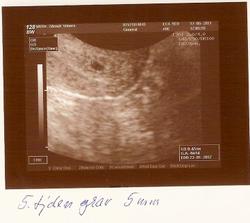

17.5. nas ceka prvni utz pro kontrolu jestli je vsechno kde ma byt🙂

Mame 4mm, vsechno zatim vypada dobre🙂 Dalsi kontrola 6.6.+ odbery.